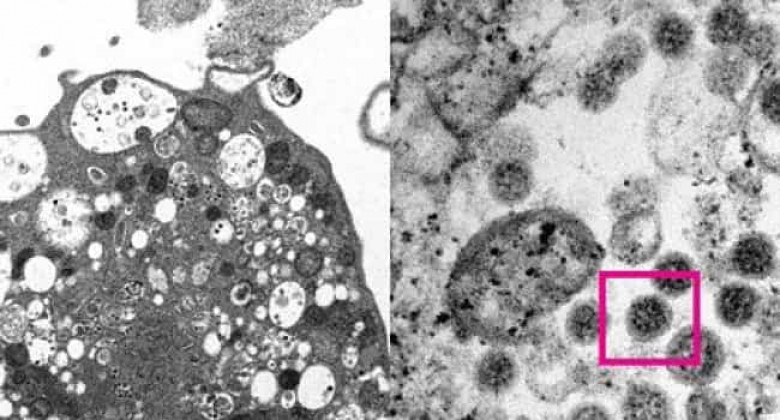

Գիտնականները լուսանկարել են կորոնավիրուսի օմիկրոն շտամը

Հոնկոնգի համալսարանի գիտնականներին հաջողվել է առաջին անգամ լուսանկարել կորոնավիրուսի օմիկրոն շտամը։ Այս մասին տեղեկացվում է գիտական հաստատության կայքում։

Հետազոտողները կատարել են կորոնավիրուսի օմիկրոն շտամով վարակված կապկի երիկամի բջջի (Vero E6) էլեկտրոնային միկրոլուսանկար։ Դրանում նրանք տեսել են վիրուսային մասնիկներ պարունակող փքված վեզիկուլներով ախտահարումներ։

Բավական մեծացնելով լուսանկարը՝ գիտնականներին հաջողվել է տեսնել բնութագրական գնդաձեւ օբյեկտների կուտակումներ՝ մակերեսին թագի նման փշերով։